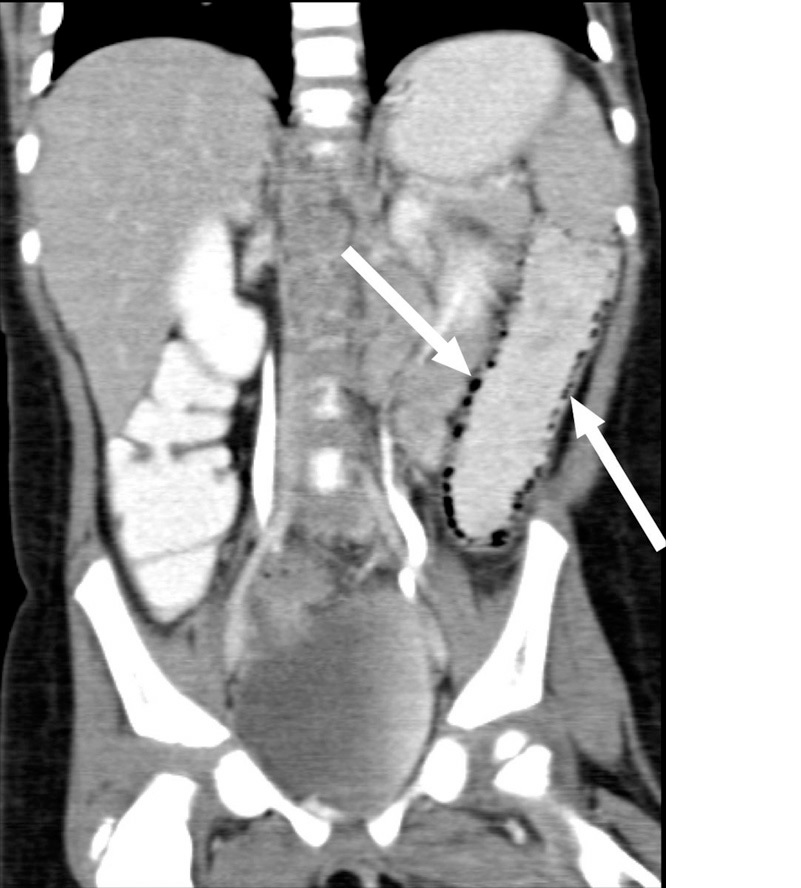

■ Henoch-Schonlein紫斑病(IgA紫斑病)と診断され、入院のうえプレドニゾロン(1mg/kg)が投与されたが、腹痛が悪化したため腹部CTが施行され、遠位小腸壁肥厚と、下行結腸の腸壁気腫が認められた。

論文から引用。下行結腸に気腫が認められる。